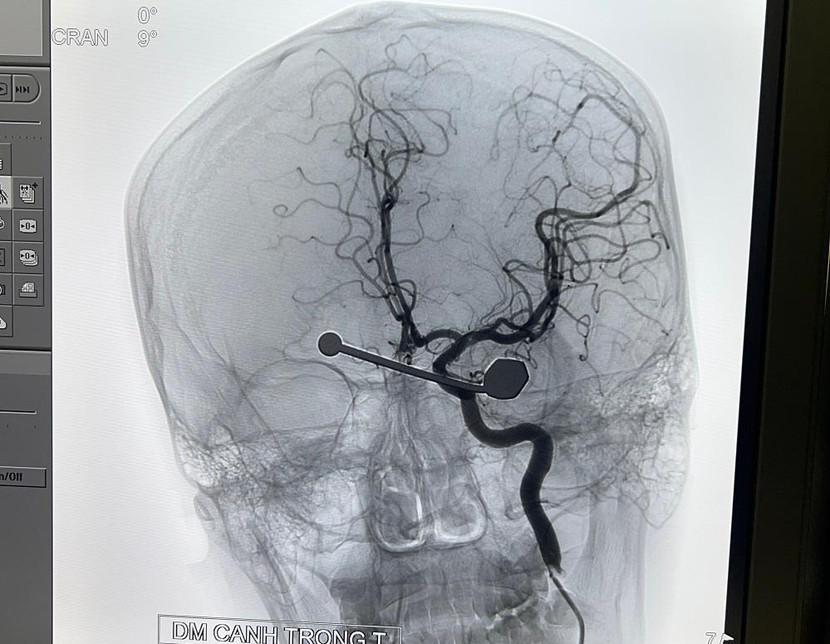

| Hình ảnh chiếu chụp cho thấy thanh dị vật cắm sâu vào mắt trái bệnh nhân |

Người bệnh được các bác sĩ chỉ định chụp cắt lớp đa dãy cấp cứu. Trên hình ảnh phim chụp cho thấy thanh dị vật dài 170x6mm, trong đó đoạn nằm trong sọ dài 120mm đi từ sát thành trong hốc mắt qua ngay dưới thành trên của xoang sàng sau bên trái xoang bướm…

Người bệnh được chuyển từ khu vực hồi sức cấp cứu xuống phòng can thiệp mạch máu, gây mê nội khí quản, đặt ống thông từ động mạch đùi lên phía các động mạch não, kiểm soát các mạch máu nằm trên đường đi của dị vật. Quá trình phẫu thuật được tiến hành tỉ mỉ nhằm hạn chế tối đa các nguy cơ có thể xảy ra.

Kết quả, dị vật được rút bỏ mà không ghi nhận có tổn thương mạch máu nào trên phim chụp kiểm tra ngay trên bàn can thiệp. Người bệnh sau đó được tiếp tục theo dõi và hồi sức tại Trung tâm Gây mê Hồi sức Ngoại khoa, chỉ định mổ cấp cứu khâu vết thương củng mạc ngay khi tình trạng sọ não ổn định.